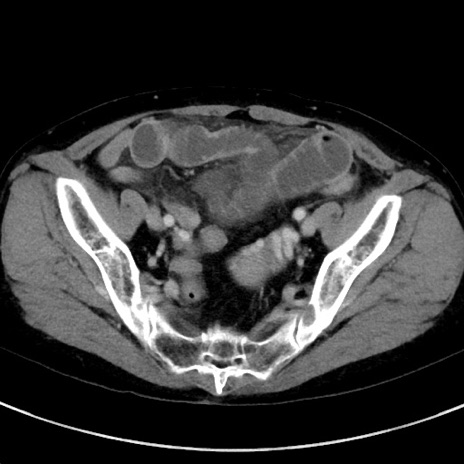

症例23(横断像)

【症例】70歳代女性

【主訴】下腹部痛・嘔吐

【現病歴】2日前より腹痛あり。昨日嘔吐あり。症状改善しないため来院。

【既往歴】胃GISTに対して胃部分切除後。

【身体所見】BT 37.1℃、BP 128/77mmHg、腹部:平坦・軟、下腹部に圧痛あり。

【データ】WBC 10200、CRP 0.31